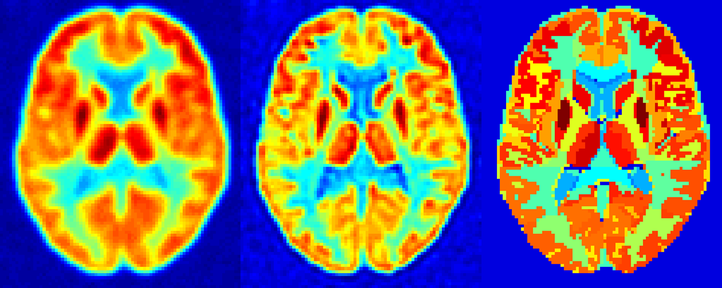

The partial volume effect is the deterioration of the image quality in a medical scan due to the limited resolution of the imaging system and the sampling of the image in discrete voxels. This results in a blurring of the image, and small structures showing a lower activity. Our group implements and develops post-reconstruction correction methods for this effect. This is done using information from the PET-scan itself (iterative deconvolution), or using anatomical information from a coregistered MRI-scan.